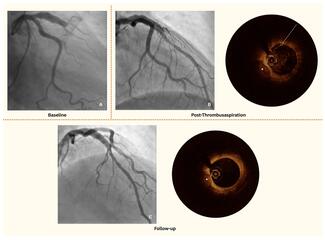

Coronary Artery Ectasia and Acute Coronary Syndrome: Insights From Optical Coherence Tomography

Coronary artery ectasia (CAE) is a dilatation of the coronary arteries that can alter flow dynamics and predispose to thrombus formation. When patients with CAE present with acute coronary syndrome (ACS), advanced imaging such as optical coherence tomography (OCT) provides valuable insight into the underlying mechanism.

See if you can identify the mechanism as illustrated in this 2025 case by Anwari et al.